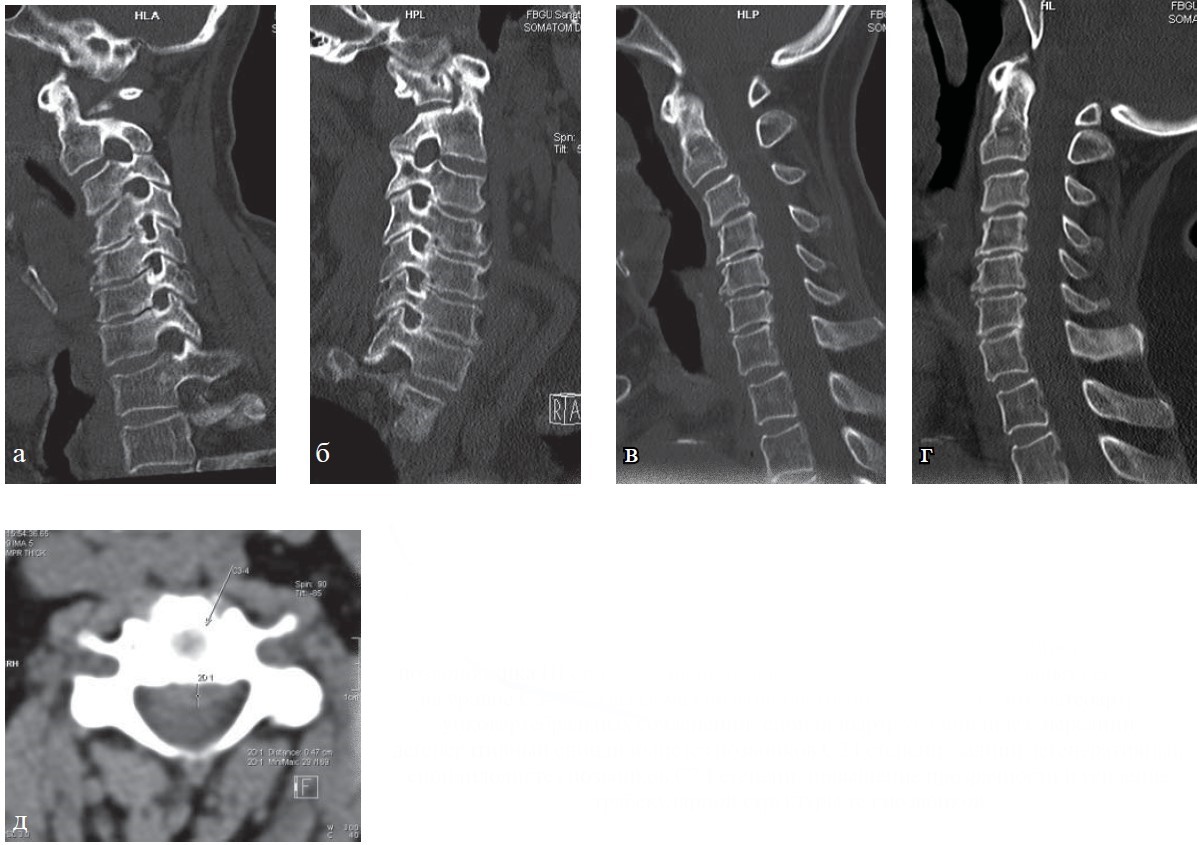

Рис. 8. КТ шейного отдела позвоночника. Больная Х., 76 лет: а, б — сагиттальная плоскость в статическом положении; в, г — при выполнении функциональных проб; д — аксиальная плоскость. Определяется остеохондроз шейного отдела позвоночника III степени с наличием гипомобильности двигательных сегментов на уровне C3—C7, грыжа межпозвонкового диска С3—4 до 5 мм, остеоартроз унковертебральных сочленений, спондилоартроз, спондилез, передний дегенеративный спондилолистез позвонков С2 I степени, задний дегенеративный спондилолистез позвонков С7 I степени, повышение прозрачности и усиление трабекулярной структуры тел позвонков.